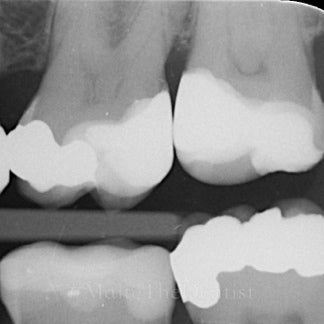

Underviser: Malte Heinrich

Fokus er på alt det, der skal sidde i kroppen, før posterior komposit bliver stabilt, effektivt og forudsigeligt i hverdagen.

• Carieseksavering med omtanke

• Form, anatomi og workflow, der gør dine fyldninger hurtigere og bedre